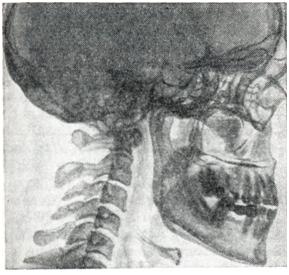

В выраженных случаях акромегалии череп большого размера. Особенно увеличен лицевой скелет (рис. 3). Рентгенологическая картина мозгового черепа приобретает пестроту в связи с перестройкой костного рисунка с преобладанием гиперостоза и утолщением диплоэ. Увеличиваются придаточные пазухи, особенно лобные. Клиновидная пазуха суживается за счет продавленности дна гипофизарной ямки. Деформируется турецкое седло: сагиттальные и вертикальные размеры увеличиваются в несколько раз, дно опускается, спинка отклоняется, истончается у основания, но рисунок верхушки спинки и прилегающей зоны усиливается за счет уплотнения костной структуры. Задние наклоненные отростки загибаются кпереди; в связи с этим на боковом снимке вход в седло кажется суженным. Контур гипофизарной ямки становится разреженным, исчезает изображение каймы компактного слоя. Следует учитывать возможность распространения опухоли вверх или в какую-нибудь сторону. Последнее выявляется по истончению и смещению на лобном снимке переднего наклоненного отростка на стороне поражения.

Рис. 3.

Череп больной акромегалией (рентгенограмма в боковой проекции).